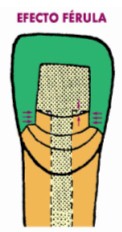

Cuando se utilizan postes prefabricados, la elección del material para

reconstruir el muñón falso, no tiene ninguna importancia desde el punto de vista

clínico, es decir que las propiedades físicas del material son irrelevantes, ya

que será el muñón remanente (efecto férula) el que se encargará principalmente

de soportar la restauración final (7).

El efecto férula es definido como un collar

metálico que rodea la periferia del diente, y que por esa característica de

abrazamiento, evita que la corona se separe en varios fragmentos (10). El

primer autor que describió en parte lo que ahora se considera efecto férula, fue

Rosen, en 1961 (30), seguido más tarde por Shillingburg en 1970 (8). Sin

embargo ellos hablaban de un “contrabisel” (Fig. 13) preparado en el muñón

remanente, que al ser abrazado por el muñón falso, mantendría al diente unido,

como lo hacen los cinchos en un barril. No fue sino hasta 1990 en que

Sorensen describió todos y cada uno de los factores que deben ser tomados en

cuenta, y que son:

-

1 mm en altura.- Debe existir

por lo menos 1 mm de altura, en sentido coronal, a partir de la línea de

terminación. Algunos autores hablan de hasta 2 mm.

-

1 mm de ancho.- Desde la pared

del conducto, hasta la pared externa de la preparación, debe haber por lo

menos 1 mm de grosor.

-

360 grados.- Las medidas antes

mencionadas deben ser consideradas en toda la periferia del diente, es decir,

en los 360 grados del mismo.

-

Paredes paralelas.- La

preparación debe ser lo más paralela posible.

-

Unión tope.- En la unión del

muñón falso con el muñón remanente de dentina, debe preparase una unión tope y

no una junta deslizante, para evitar que en cualquier instancia, el muñón

falso/poste se intruya en la raíz.

- Dentina sana.-

Los cinco puntos mencionados antes, deben ser logrados en dentina sana (Fig.

14).